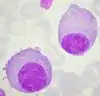

.png.webp) |

B Cell | Lymphocyte | B Cell |

|

8-10 |

|

[14][4] |

T Cell | Lymphocyte | T Cell |

|

8-10 |

|

[4][17] |

|

Memory T Cell | Lymphocyte | T Cell |

|

8-10 |

|

[4][18] |